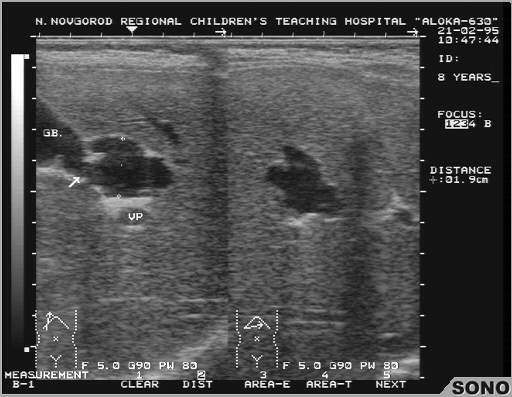

Холедохолитиаз